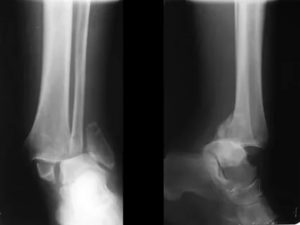

- Рентгенографии пораженного сустава (применяются две проекции — боковая и передне-задняя);

Для проведения дифференциальной диагностики проводится рентгенография. На рентгеновском снимке видны признаки нарушения целостности костей.

Для уточнения характера повреждений, особенно если трехлодыжечные переломы осложняются смещением костных отломков или подвывихом, рентгеновский снимок голеностопного сустава делается в трех проекциях. Данные рентгенографии позволяют врачу выбрать оптимальную тактику лечения больного.